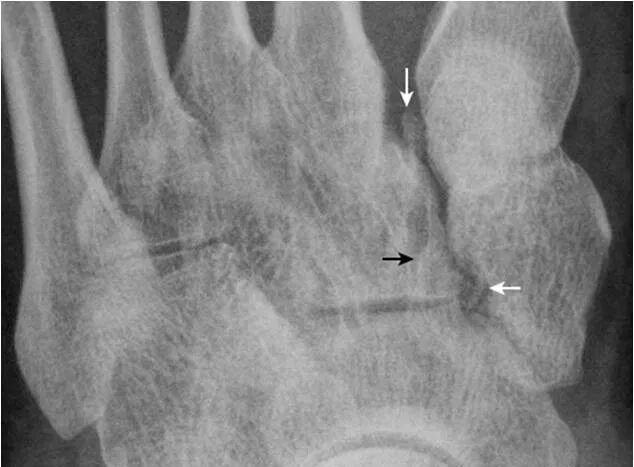

6.楔骨间骨:

为内侧及中间楔骨间副骨,边缘光滑(箭),属正常变异。内侧楔骨前内缘致密影(双箭头)为胫骨前肌肌腱附着处后缘的切线位投影,非病变。内侧楔骨与舟骨间见楔舟内侧骨(箭头)。